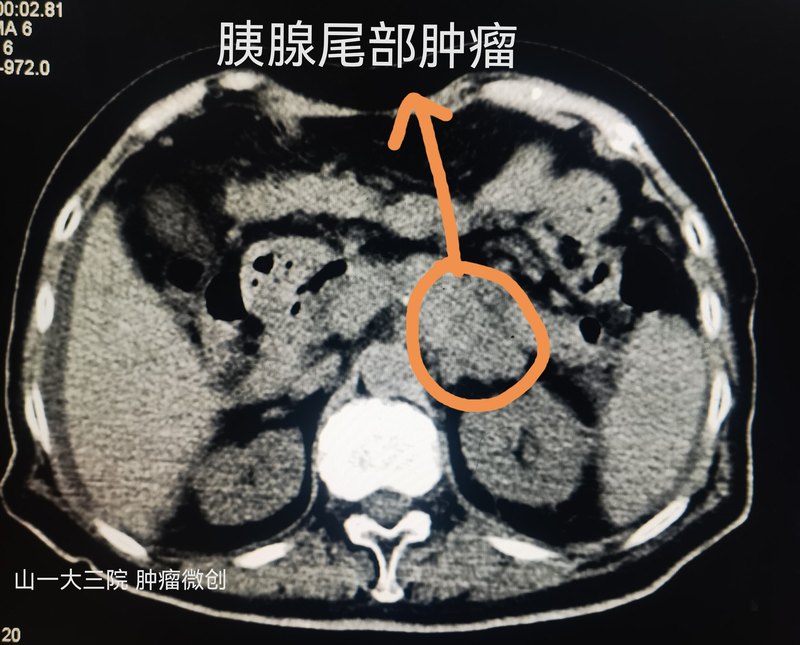

胰腺穿刺難度系數(shù)較高,因?yàn)橐认賗con位置比較深,位于腹腔正中靠后的地方,而且周?chē)际侵匾钠鞴俸痛笱埽胺绞俏负褪改c,后方有大動(dòng)脈,有椎體。進(jìn)針的道路也很難抉擇。這是一例胰腺尾部的腫瘤,最大直徑約4cm,侵犯了小腸和周?chē)牧馨脱?,需要穿刺明確病理診斷。做好這個(gè)胰腺穿刺的關(guān)鍵有以下幾點(diǎn):1:提前一天充分的腸道準(zhǔn)備2:提前一天用上抑制胰液icon分泌的藥物3:術(shù)前要用止血藥4:術(shù)中選擇合適的穿刺路徑,能穿刺胃,不穿刺小腸,能穿刺小腸不穿刺大腸,盡量不經(jīng)過(guò)脾臟,可以通過(guò)腎臟脂肪囊。5:術(shù)中要分次進(jìn)針。6:術(shù)后繼續(xù)禁飲食三天,用抑制胰液的藥物。這個(gè)患者還是比較幸運(yùn)的,術(shù)后沒(méi)有出現(xiàn)并發(fā)癥,細(xì)胞學(xué)icon和病理也很理想,為后續(xù)的規(guī)范化療打下了基礎(chǔ)。